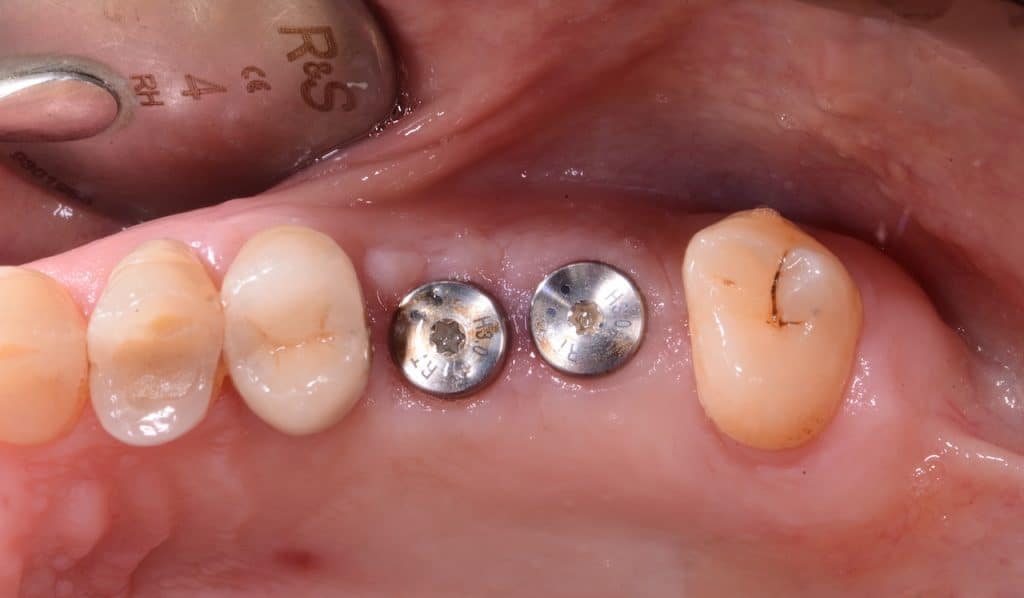

occlusal view, implants placed

- Two 8 mm Straumann TLX implants placed

- TLX implants have an excellent primary stability in most cases (as post-extraction cases). But in the case of sinus lift they tend to lose primary stability in the last stages of screwing. Therefore in this case a conical implant is preferable.